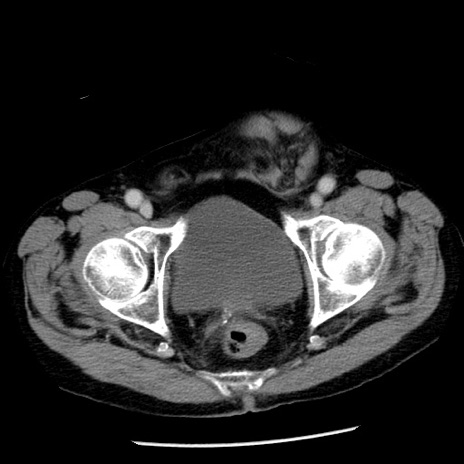

冠状断像

【症例】80歳代男性

【主訴】嘔吐

【現病歴】昨晩2回嘔吐あり、今朝になっても嘔吐あり。来院。

【既往歴】胃潰瘍

【身体所見】意識清明、BT 37.6℃、BP 166/95mmHg、HR 100bpm、SpO2 97%、腹部:平坦・軟、腸蠕動音聴取良好、圧痛なし。

【データ】WBC 21900、CRP 1.46